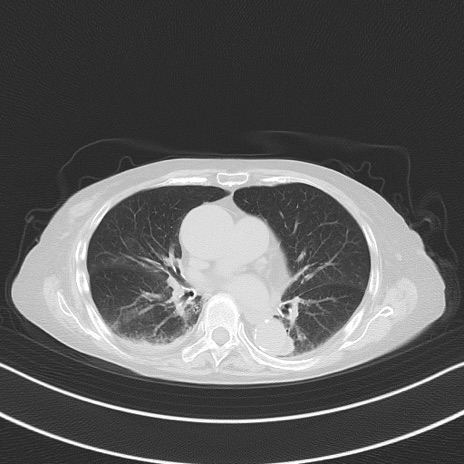

横断像

他院CT